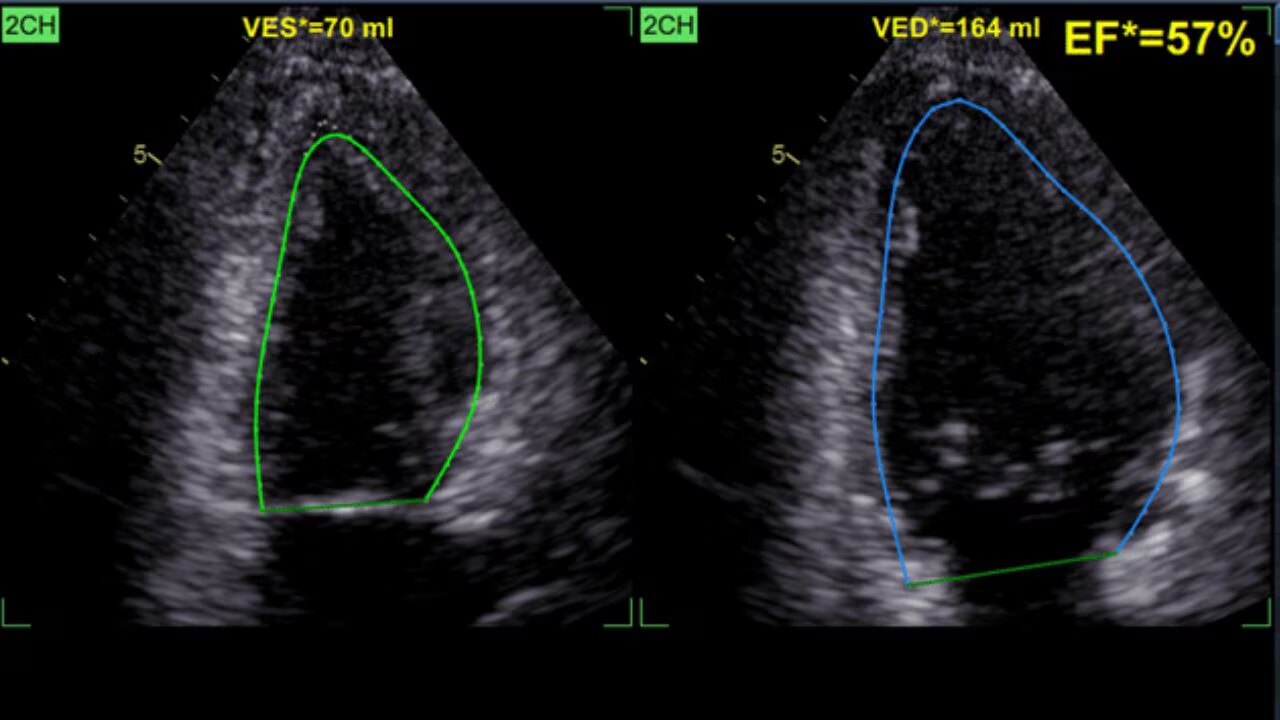

Our latest AI-based technologies can help improve workflow efficiency

The new Vivid T series ultrasound systems have been designed to meet today’s challenges. To allow more quality time with patients, increase diagnostic confidence, and reduce inter-operator variability - all at a price point accessible for private practices.

The Vivid T series cardiovascular ultrasound has been designed to meet today’s challenges. The Vivid T series allows more quality time with patients, increases diagnostic confidence, and reduces inter-operator variability - all at a price point accessible for private practices.

ViewPoint EchoPilot is cloud-based solution that auto-generates precise measurements and delivers a preview of your routine echocardiogram report in just seconds. Experience it with the Vivid T9!